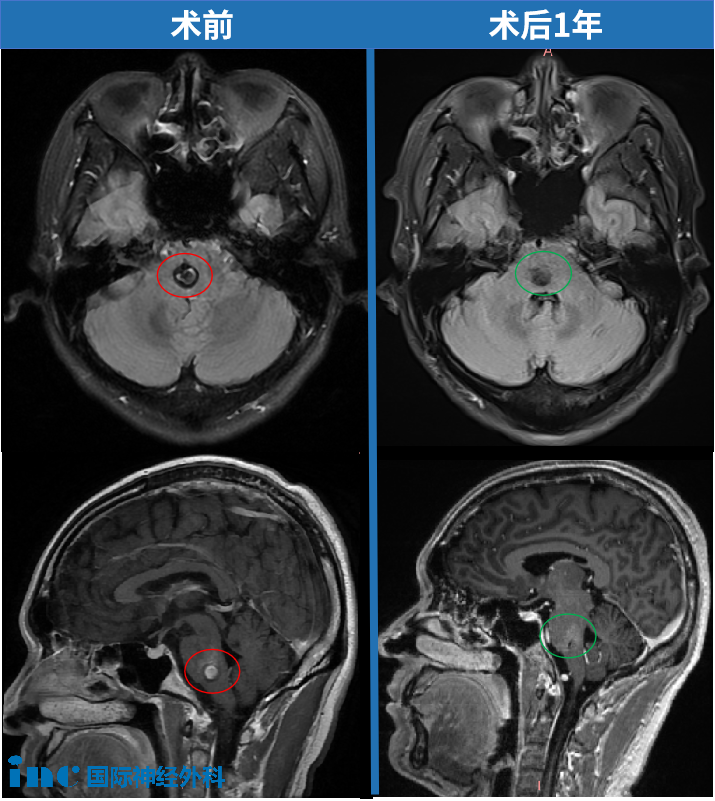

刘先生凑近屏幕,看到脑干位置有一个约1公分大小的异物清晰可见。他赶忙又跑去隔壁CT室复查,“我当时一看就像血管瘤的样子,很震撼,接受不了。”当诊断明确为脑干桥脑海绵状血管瘤,他比任何人都清楚这个区域手术的风险。但也正因如此,他更明白:若想真正解决问题,手术几乎是唯一的路。

2023年12月,刘先生因为轻微的手指麻木查出脑干(桥脑)海绵状血管瘤并出血,病灶0.8cm。不到一个月的时间,刘先生麻木症状开始扩大到手掌、手臂、甚至到下肢。期间,多次复查,病灶也在增大,约1.5x1.2cm。

INC巴特朗菲教授带领苏州大学附属第四医院神经外科团队,默契的配合下,用20多年前他就发明的一种手术入路,为刘先生顺利全切脑干海绵状血管瘤——这场高难度开颅手术成功了!而术后的刘先生,从手术室到ICU再到普通病房,巴教授每一次查房,他的手越来越有力,不适症状也一点点改善。